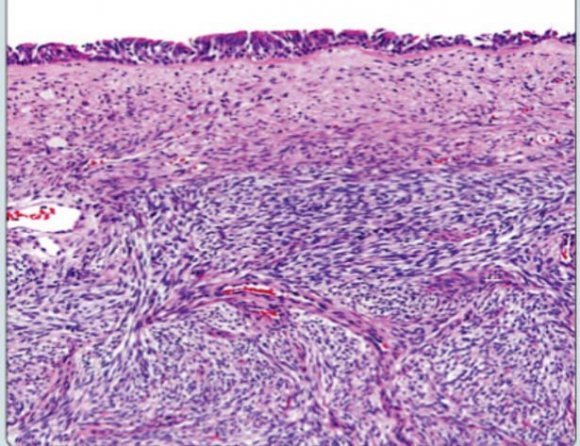

Histopathological examination of the biopsy showed features of juvenile angiofibroma, rarity of such tumors in a female prompted us to have slides reviewed, which was reported the same.

Histopathological examination result of specimen was initially reported as Angiofibroma. The rarity of angiofibroma in females and a doubt in certain slides compelled our chief pathologist to get specimens reviewed at Harvard Medical School and they diagnosed it as one of the rare and newly discovered entity i.e. Biphenotypic Sinonasal Sarcoma (SNS).